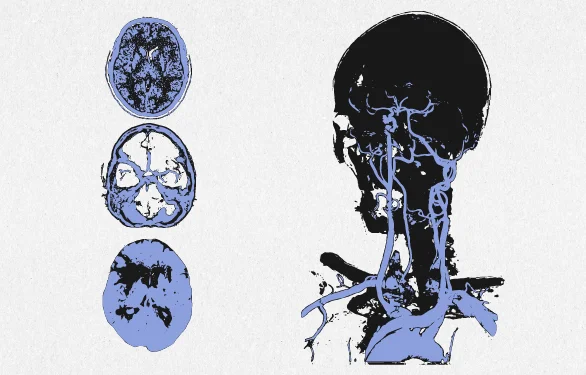

Рассеянный склероз является хроническим заболеванием, поражающим центральную нервную систему. Им болеют более 3 миллионов человек в мире, соотношение заболеваемости мужчин и женщин составляет 1 к 3.

Рассеянный склероз означает нарушение защитной оболочки, которая окружает нервные волокна в головном и спинном мозге. Повреждение вызывает рубцы, в результате чего нервы не посылают сигналы в наш мозговой центр должным образом. Рассеянный склероз непредсказуем и каждого человека атакует по-разному. Одних людей болезнь слабо затрагивает, в то время как другие теряют способность писать, говорить и ходить. Это требует адаптации жизни, но при правильном уходе и помощи близких большинство больных с диагнозом рассеянный склероз способны вести прежнюю жизнь.

ПАТОГЕНЕЗ РАССЕЯННОГО СКЛЕРОЗА

Чтобы понять причины развития рассеянного склероза в организме, ознакомимся с его анатомией.

Для того, чтобы рассеянный склероз стал болезнью, поражающей центральную нервную систему, нужно чтобы что-то изменило проницаемость гематоэнцефалического барьера, который препятствует проникновению чужеродных, ядовитых веществ и соединений, в том числе и лекарств, способных навредить клеткам головного и спинного мозга. В результате изменения этой проницаемости возникает рассеянный склероз.

ДИАГНОСТИКА РАССЕЯННОГО СКЛЕРОЗА

Поставить подтвержденный диагноз рассеянного склероза непросто, так как ранние симптомы могут быть незначительными или повторяющимися от случая к случаю. Иногда для диагностики требуются годы. Кроме того, другие заболевания имеют похожие клинические признаки, и нет однозначного лабораторного теста для подтверждения. Пациенту будет поставлен диагноз рассеянный склероз, если есть соответствующие клинические признаки и этому нет иного объяснения.